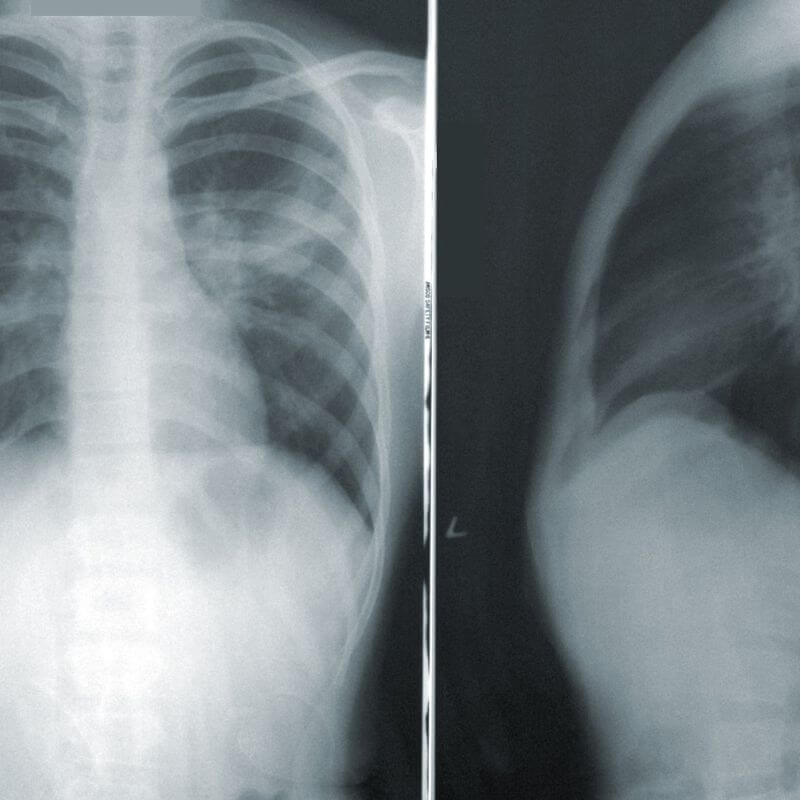

Los rayos X son un tipo de radiación electromagnética similar a la luz visible. Sin embargo, a diferencia de la luz, estos rayos tienen mayor